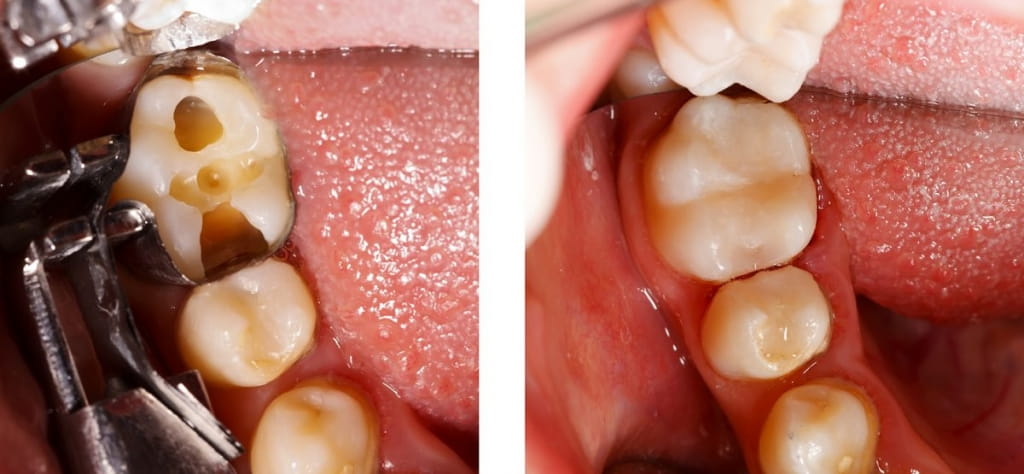

White Fillings

We use fillings to replace and restore your tooth structure damaged due to decay or fracture. But gone are the days of a mouth filled with metallic fillings. We use state-of-the-art, tooth-colored resin or porcelain materials to fill the hole or fracture, eliminating unsightly and unhealthy silver/mercury fillings and giving you a more natural looking smile.